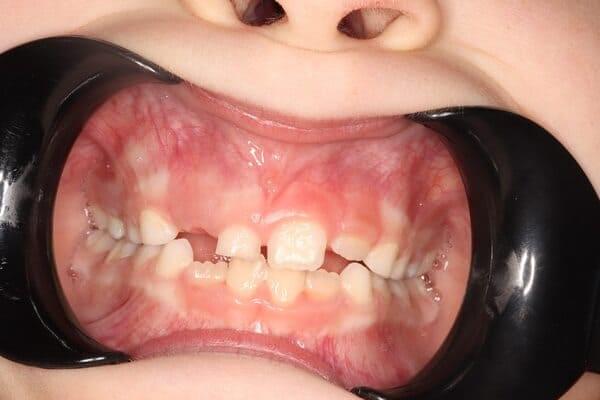

Один рік і два місяці вік дитини. Хтось скаже: «Що там тим зубам можна лікувати?!» Однак є ситуації, коли каріозний процес розвивається просто блискавично. Часто це пов’язано з порушеннями у формуванні твердих тканин ще внутрішньоутробно. А коли такі зубчики прорізуються, руйнування відбувається просто «на очах». Вісім із восьми зубів уражені, а 4 з них потребують часткового видалення пульпи («нерва»). На цьому етапі зуби вже починають турбувати і не зважаючи на юний вік дитини, зволікати не можна. Завдяки високій компетенції наших анестезіологів, які працюють з дітьми від самого народження і навіть з передчасно народженими, ми можемо проводити відповідне лікування в анестезіологічному забезпеченні за потреби навіть з першого зуба. Верхнім зубчикам, які сильно уражені, служити до 7-8 років, тому вони покриваються стандартними естетичними цирконієвими коронками, які дають максимальний результат по надійності, функції та естетиці. Година з половиною роботи і дитина може знову кусати без болю і дискомфорту. Важливо пам’ятати: для лікування зубів ніколи не буває “зарано”, це потрібно робити тоді, коли є відповідні показання